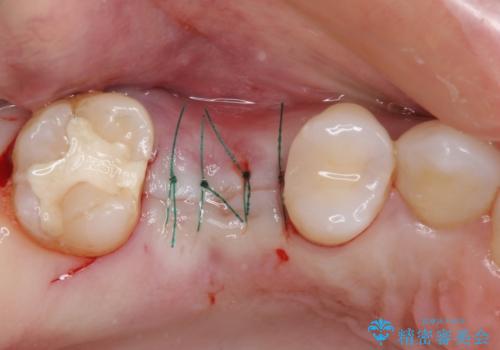

診察の結果、大きな虫歯となっている歯は抜歯が望ましく、抜歯後にストローマンSLActiveを埋入することとしました。

- 外科手術のため、術後に痛みや腫れ、違和感を伴います